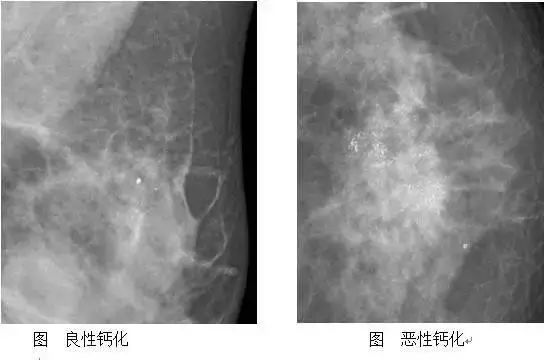

5.钙化

解读:散在点状的、孤立的、大的、圆圆的钙化(钼靶片子上白色的小点点)其实都是良性的钙化,虽然一旦产生就不会消失,但终生也不会恶变,也不需要管它。有问题的恶性“钙化”是非常少见的,不过,可疑恶性的钙化一定需要医师进一步的处理。